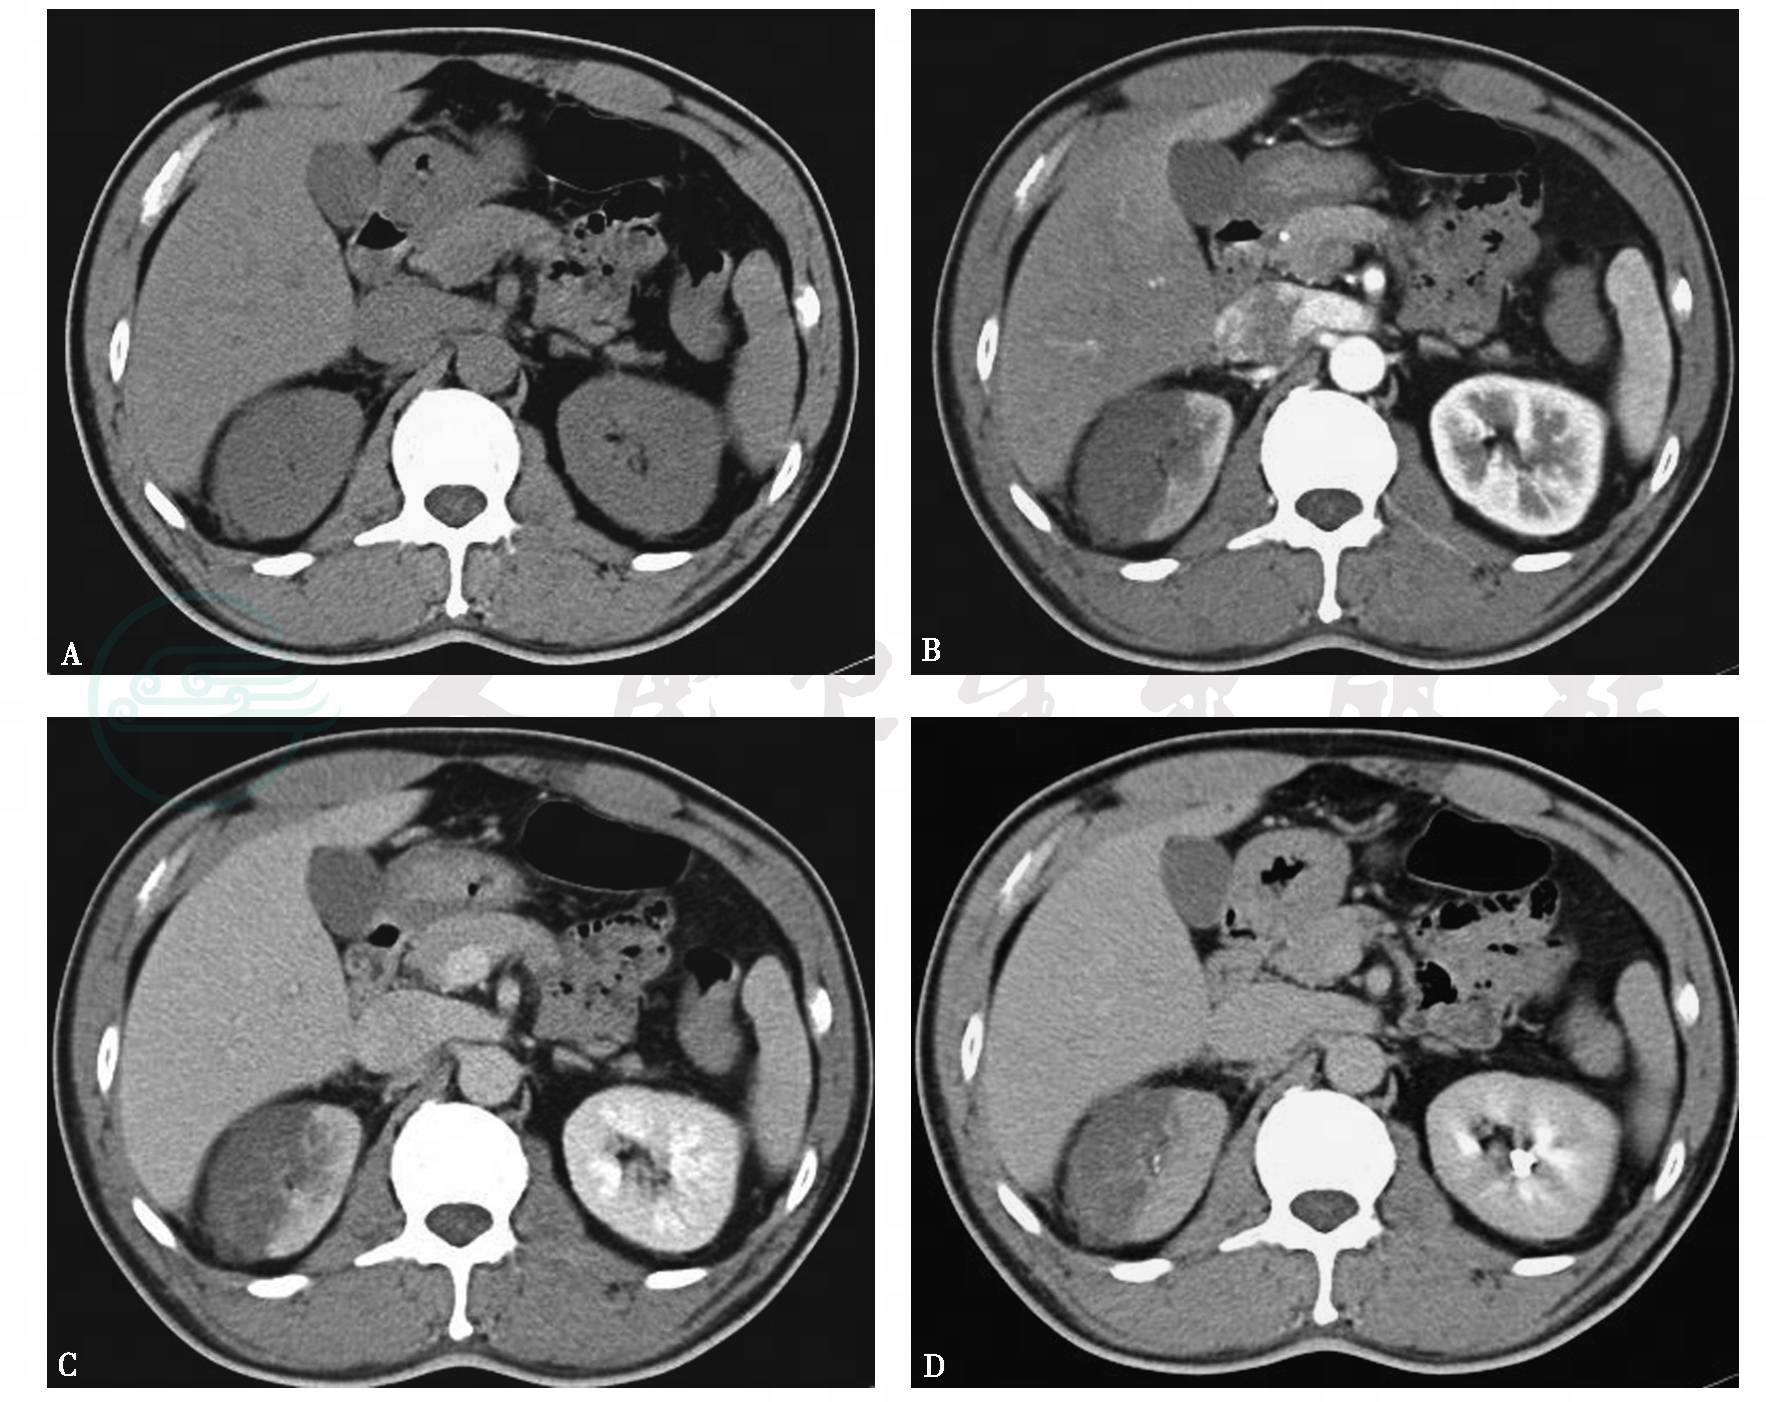

图1右肾梗死

A.平扫,双肾形态、大小、密度尚可,右肾周可见条状等密度影;B~D.增强,右肾上极可见扇形无强化区,尖指向肾窦

引自:泌尿系统多层螺旋CT诊断学.第1版.ISBN:978-7-117-24109-0.主编: